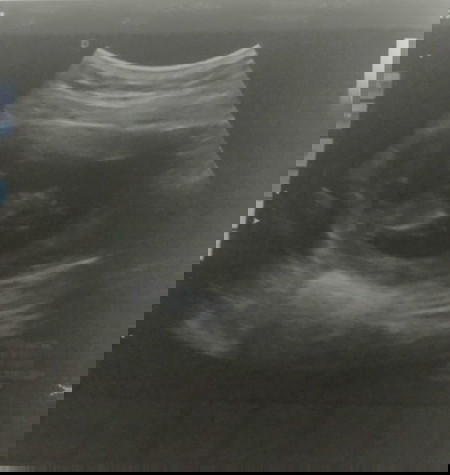

แท้งคุกคาม

น้อง12+3wตื่นเช้ามีเลือดออกรีบอาบน้ำไปพบคุุณหมอผลซาวด์น้องดิ้นดี หัวใจเต้นดีแข็งแรงปกติแต่คุณแม่เลือดออกแต่ไม่ปวดท้องใครมีประสบการณ์แบบนี้แล้วเป็นอย่างไรบ้าง#ช่วง5wแท้งคุกคามฉีดยากันแท้งทุกอาทิตย์-8wตอนนี้กลับบ้านนอนนิ่งๆขอกำลังใจด้วยค่ั